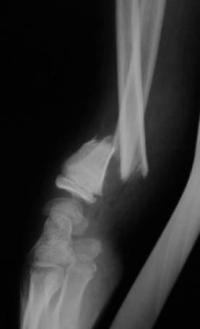

Métaphyse poignet -1 Radio post-opératoire Profil

Radio post-opératoire après embrochage intrafocal du radius et centro-médullaire de l'ulna